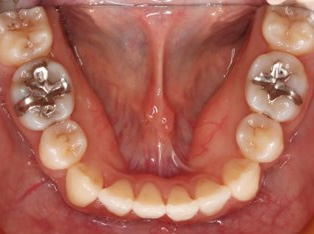

治療前

治療終了前

下顎が上顎より前に出ている状態です。お顔つきも、下顎の先(オトガイ)が前に出ているような横顔になる場合が多いです。前歯が咬んでいないことが多く、奥歯への負担が大きい状態になります。そのままのかみ合わせを続けてしまうと、奥歯がかけたり、割れたりするリスクが高まります。歯列矯正では奥歯の位置をコントロールし、前歯のかみ合わせを作る治療方針を立てます。ごく稀に、歯列矯正ではかみ合わせを作れない場合もあり、その場合は外科矯正という手段を用いて矯正治療をしなければいけません。受け口は、遺伝性が強いとも言われておりますので、そういった情報も考慮し、治療を進めていくことが大切です。